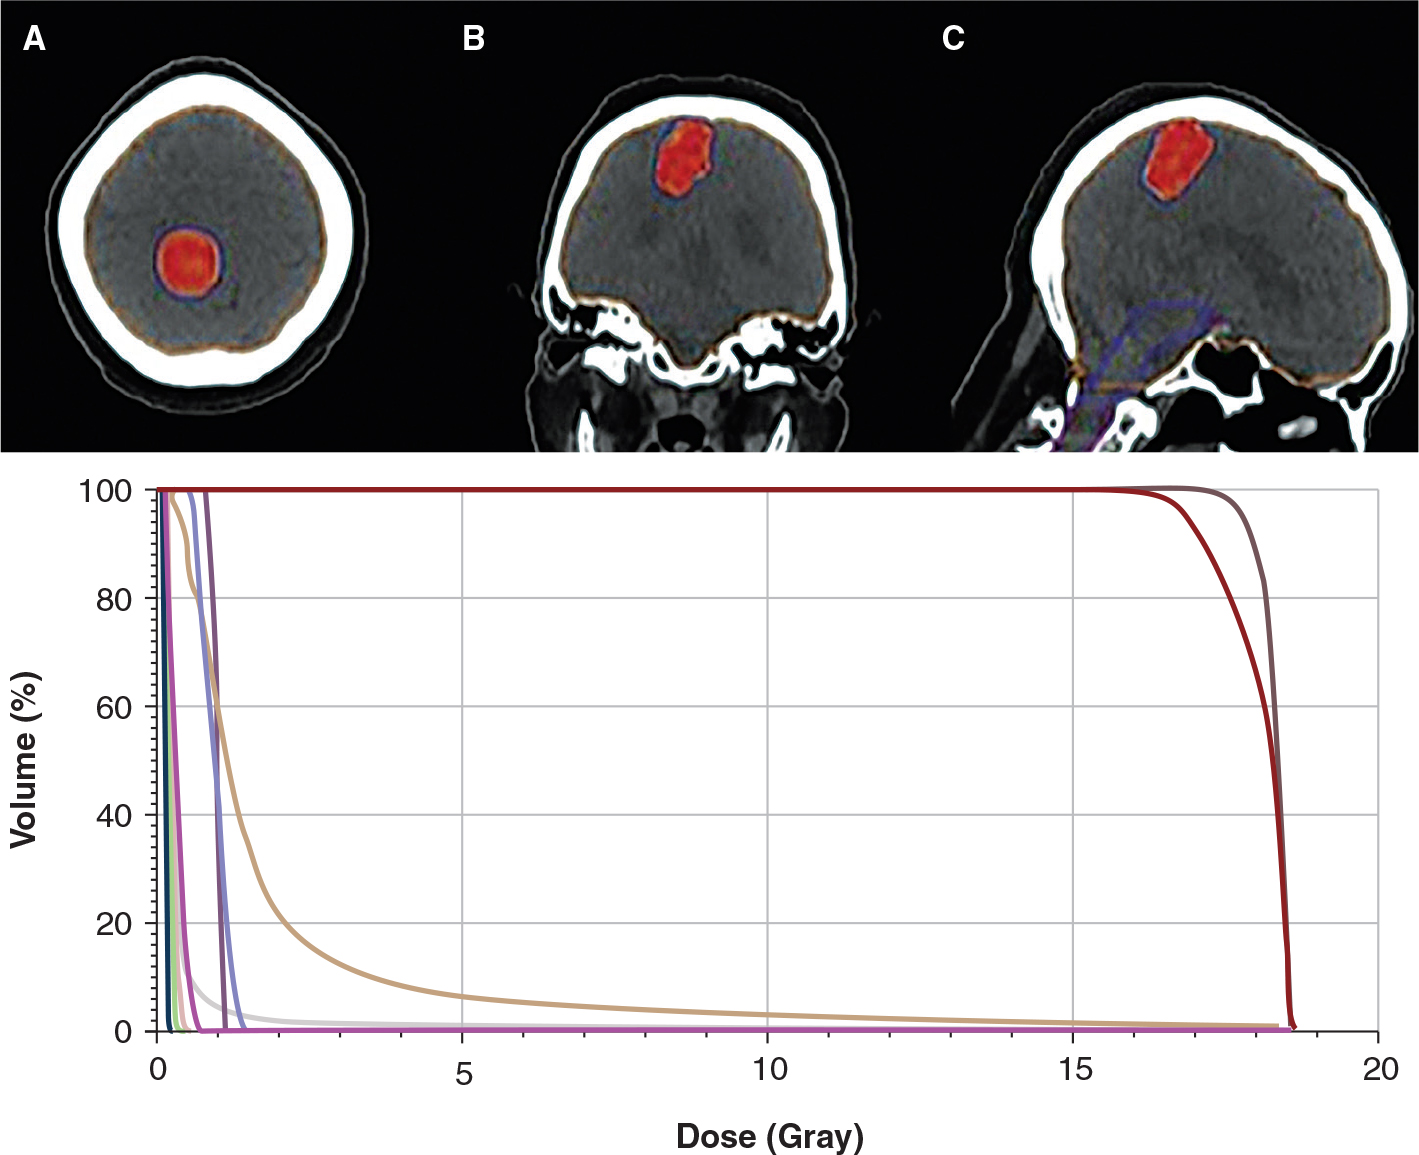

Brain metastasis occurs in 30–40% of adult patients with solid cancers (1, 2). Lung cancers (small and non-small cell), malignant melanoma (MM), renal cell carcinoma (RCC), and breast cancer are the most common causes of brain metastasis (3). Chemotherapy, surgery, whole-brain radiotherapy (WBRT), stereotactic radiosurgery (SRS), targeted therapies, and immunotherapy are used to treat brain metastasis (4, 5). SRS is used more frequently in clinical practice because it produces better results with less toxicity than WBRT (6) (Figure 1). The main mechanisms by which the ionizing radiation used in WBRT functions are double-strand DNA damage, ‘oxygen fixation’ of the damage, and the production of cytotoxic free radicals in tumor cells. When ionizing radiation is used in the form of high-precision SRS, it affects the local and systemic immune responses against the tumor cells by inducing immunogenic cell death, improving neoantigen presentation, and activating cytotoxic T-cells (7). In comparison to conventional WBRT, SRS offers better local control rates with a lower risk of neurocognitive decline (8). Given this foundational understanding, several authors recently discussed their experiences using various combinations of immune checkpoint inhibitors (ICIs) and SRS in patients who presented with brain metastasis from various cancers. As a result, it has been proposed that immunoradiotherapy may facilitate a higher local control and an antitumor systemic response by activating the adaptive immune system through T-cells (7). The goal of the current chapter is to summarize our current knowledge on the role of combined SRS and ICIs for the treatment of brain metastasis.

Fig 1

Figure 1. A typical linear accelerator based stereotactic radiosurgery plan and related dose-volume histogram for a patient with single brain metastasis. A: Axial; B: Coronal; C: Sagittal view.